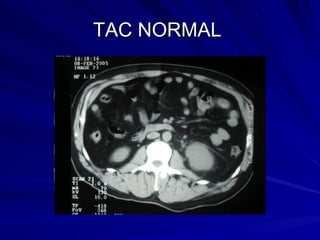

TAC NORMAL